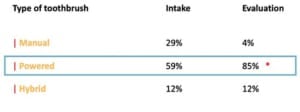

Stap 4 bestaat uit nazorg waarbij eerst de situatie wordt beoordeeld. Het is ook belangrijk dat de patiënt zelf zorgt voor supragingivale plaquecontrole door middel van het begeleiden van de patiënt met het gebruik van een elektrische tandenborstel en cilindrische ragers. Het bijsturen van de motivatie en instructie is een belangrijk onderdeel van de nazorgbehandeling. Uiteraard wordt er een professionele gebitsreiniging uitgevoerd, sub en supragingivaal. Bloeding na sonderen is daarvoor een belangrijke parameter. Uiteindelijk voor een nazorg behandeling afgerond met polijsten en op inidctaie het aanbrengen van fluoride. Ten slotte wordt een recall interval wordt bepaald tussen 3 en 12 maanden. Belangrijke factoren om dit interval te bepalen zijn roken, diabetes, aantal pockets > 5 mm, BOP% en hoeveelheid botverlies. Om deze stappen binnen de nazorg goed te kunnen doorlopen en voldoende tijd te kunnen besteden aan alle aspecten is het zo genoemde “profy hour” bedacht.